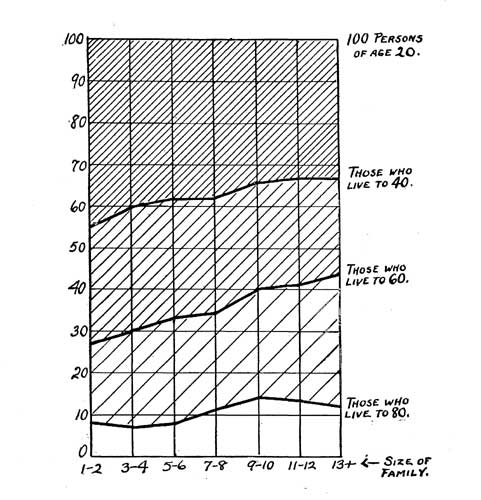

| 43. Adult Morality | 345 |

| 44. Influence of Mother's Age | 347 |